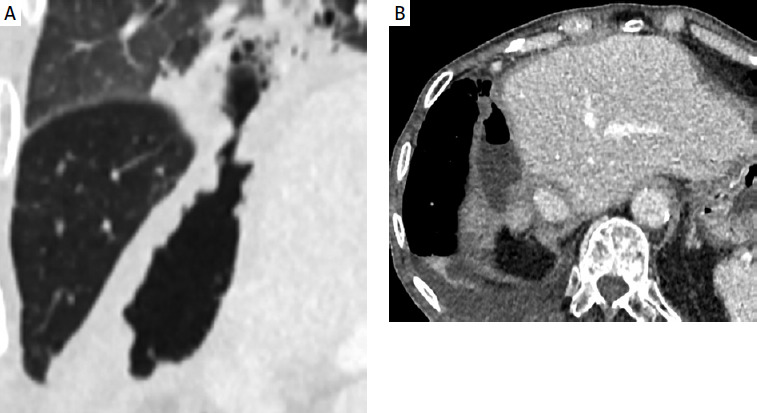

Ethics board approval for preparation of this case report was waived. A 74-year-old male patient with a history of rectal cancer and synchronous right lobe liver metastases underwent initial treatment with three lines of chemotherapy, a liver wedge resection, and a lower anterior resection. Three years later, a 9.7 cm right lobe colorectal liver metastasis (CLM) was identified, approximately 2.75 mm from the colon (Figure 1). The patient was referred to interventional radiology for consideration of locoregional therapy.

Figure 1

A – Baseline contrast-enhanced axial computed tomography (CT) with a 9.7 cm colorectal liver metastasis. B – Baseline contrast-enhanced coronal CT with the distance from the colon